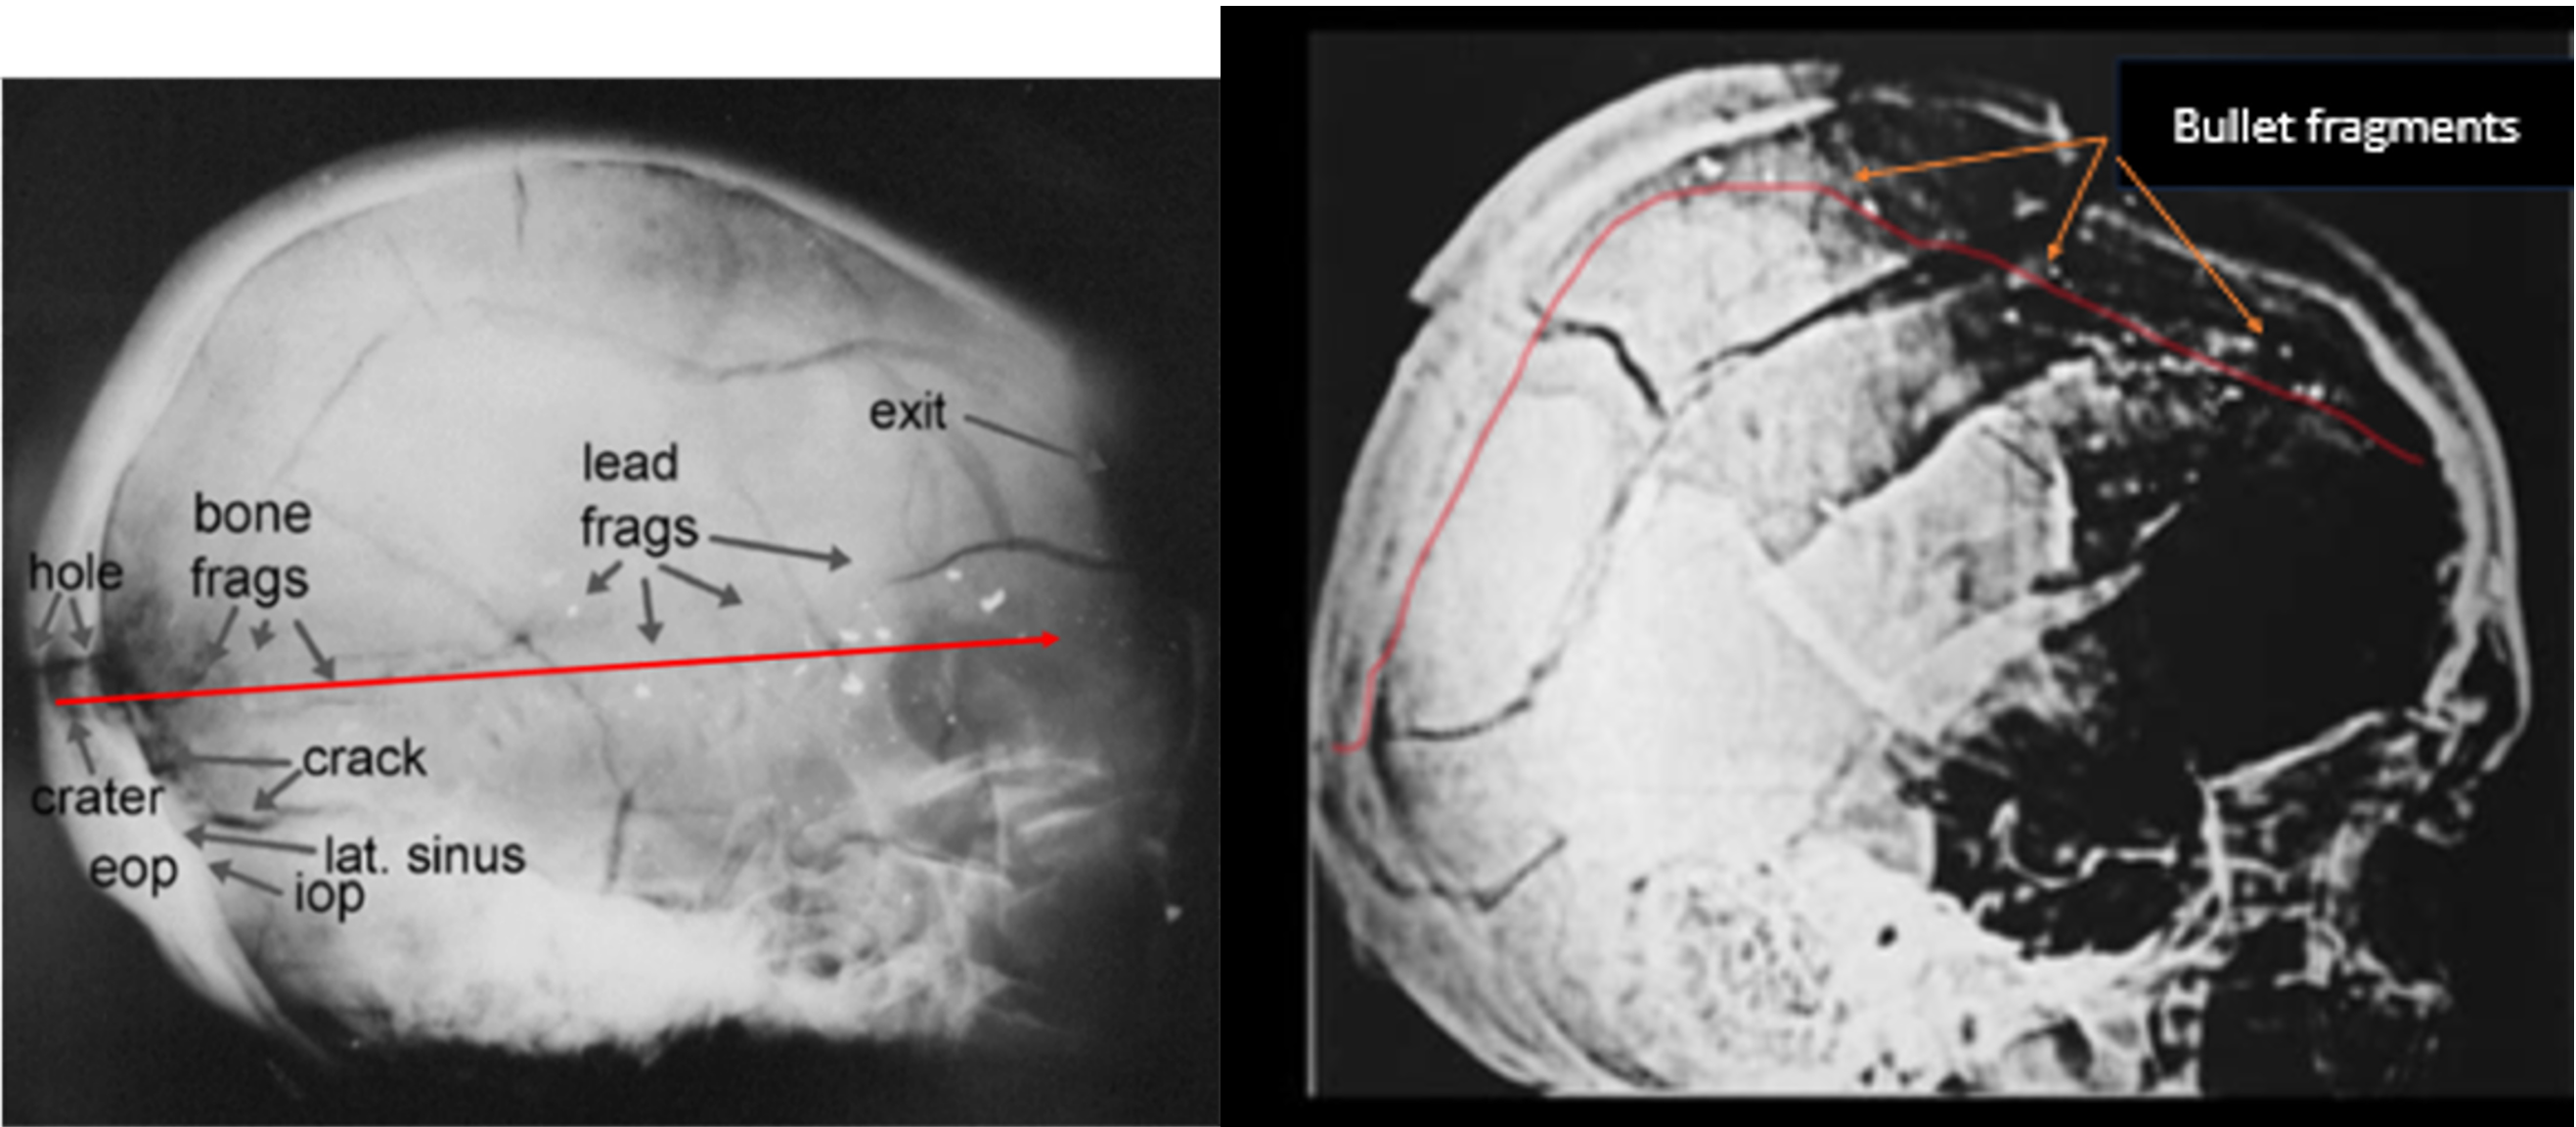

JFK’s X-rays can’t keep Wagner’s ship afloat. A test skull shot with a Carcano round showed no “dust-like,” no “snowstorm,” of minuscule fragments. Wagner’s own expert, Larry Sturdivan, testified in detail why: jacketed bullets like Oswald’s don’t leave a “snowstorm” of minuscule fragments after blasting through bone.[28]

But in fact, there is a “snowstorm” of minuscule bullet fragments in the right front quadrant of JFK’s skull X-ray. They are clearly visible in JFK’s original, unenhanced X-rays, and their existence in that location was attested to by expert radiologists.[29] But they’re blotted out and are not visible in the poor quality, “enhanced” films available to the public.

Moreover, jacketed shells like Oswald’s don’t deviate much from their original flight path. Why? Because, as Larry Sturdivan testified, the jacketed “Mannlicher-Carcano bullet is much more stable, the yaw begins to grow much more slowly (than non-jacketed, military rounds do) … .”[30] (my emphasis)

Wagner asks us to believe that Oswald shot downward toward JFK’s receding skull, striking it low with a jacketed slug. It was then somehow deflected way upward to the top of JFK’s skull, leaving fragments high in the skull. (Figs.7&8)

Figure 8. Left: Sturdivan reproduced an X-ray of a test skull shot with a Mannlicher round at the Biophysics Lab.[31] The fragments are small, but not “dust-like.” Not like the “snowstorm” of fragments visible in the right-front quadrant of Kennedy’s still-secret, original and unenhanced, lateral X-ray. (Which is evidence JFK was killed with a non-jacketed bullet. For “dust-like” fragments are quickly stopped by brain tissue, and so lodge close to the point of entry.) Moreover, the test skull’s fragment trail closely follows a low, little-deviated flight path across the skull, precisely as Larry Sturdivan said happens with MCC rounds.

* Right: JFK’s “enhanced” lateral X-ray: small fragments are visible only along the top of the skull. Wagner says that, unlike the test skull, Oswald’s bullet was fired downward, struck JFK’s skull low, then popped up to the top of his skull, broke apart, and blew out of the right side of his head.

- That Oswald’s bullet entered Kennedy’s skull low on a downward trajectory, yet was wildly deflected upward. Which is in defiance of the expressed claims of Wagner’s experienced, government ballistics expert, Larry Sturdivan, whose opinion was confirmed in a government duplication test that showed that a Mannlicher shell was not deflected as it passed through a human skull;

- That Oswald’s jacketed MCC bullet left a “snowstorm” of minuscule fragments in the right front quadrant of JFK’s head when “snowstorms” in X-rays are not seen with jacketed bullets, but only with non-jacketed rounds. [Nor was a “snowstorm” seen in the X-ray of a test skull shot with an MCC shell in a government test. (Fig.8)]